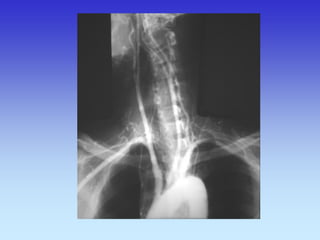

PROFILNA SNIMKA GLAVE